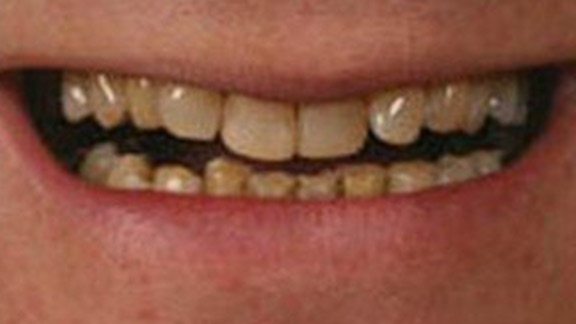

Smile Restoration

Smile Restoration Case 1

Smile Restoration Case 2

Smile Restoration Case 3

Smile Restoration Case 4

Smile Restoration Case 5

Smile Restoration Case 6

Smile Restoration Case 7

Smile Restoration Case 8

Smile Restoration Case 9